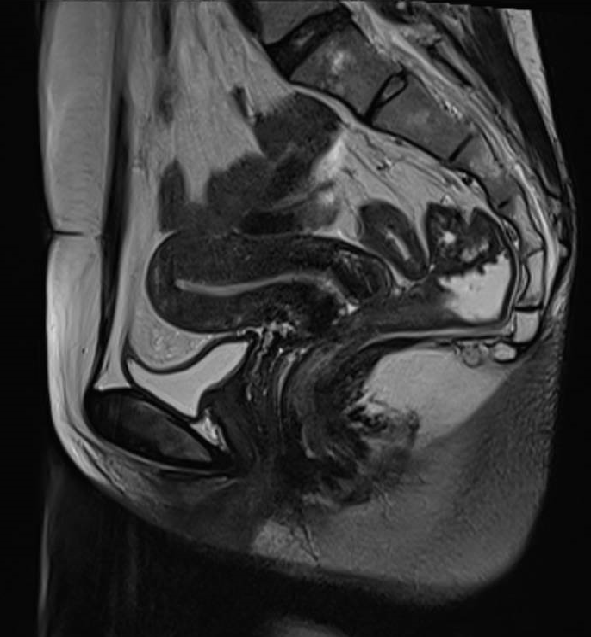

盆腔MRI提示宫颈肥厚,肿瘤性病变不除外